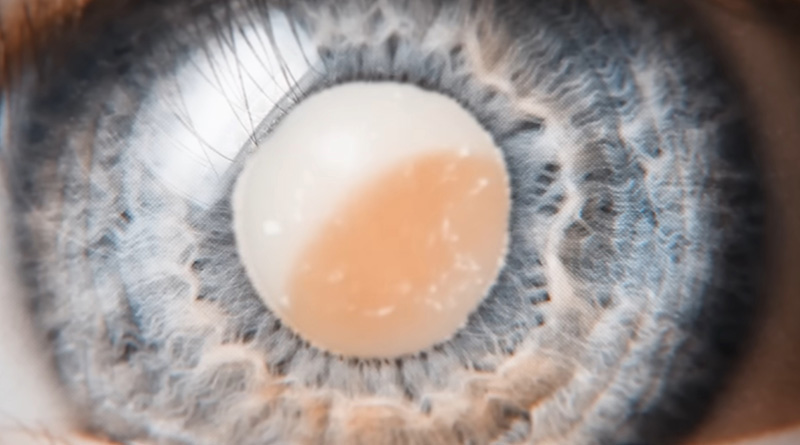

ซึ่ง MrBeast กล่าวว่า ประชากรบนโลก 200 ล้านคน มองเห็นโลกแบบมัว มีปัญหาทางสายตา แต่ 50% สามารถรักษากลับมามองเห็นได้เพียงใช้เวลาผ่าตัดแค่ 10 นาทีเท่านั้น ศัลยแพทย์จะใช้เครื่องดูดเลนส์ที่มัวออก แล้วใส่เลนส์ตาเทียมเข้าไปแทน เลยได้เห็นปฏิกิริยาของคนทั้ง 1,000 คน ที่กลับมามองเห็นอีกครั้ง และยังให้เงินอีก 10,000 ดอลลาร์ เรียกว่าเป็นคลิปที่ทำเอาน้ำตาซึมเลย